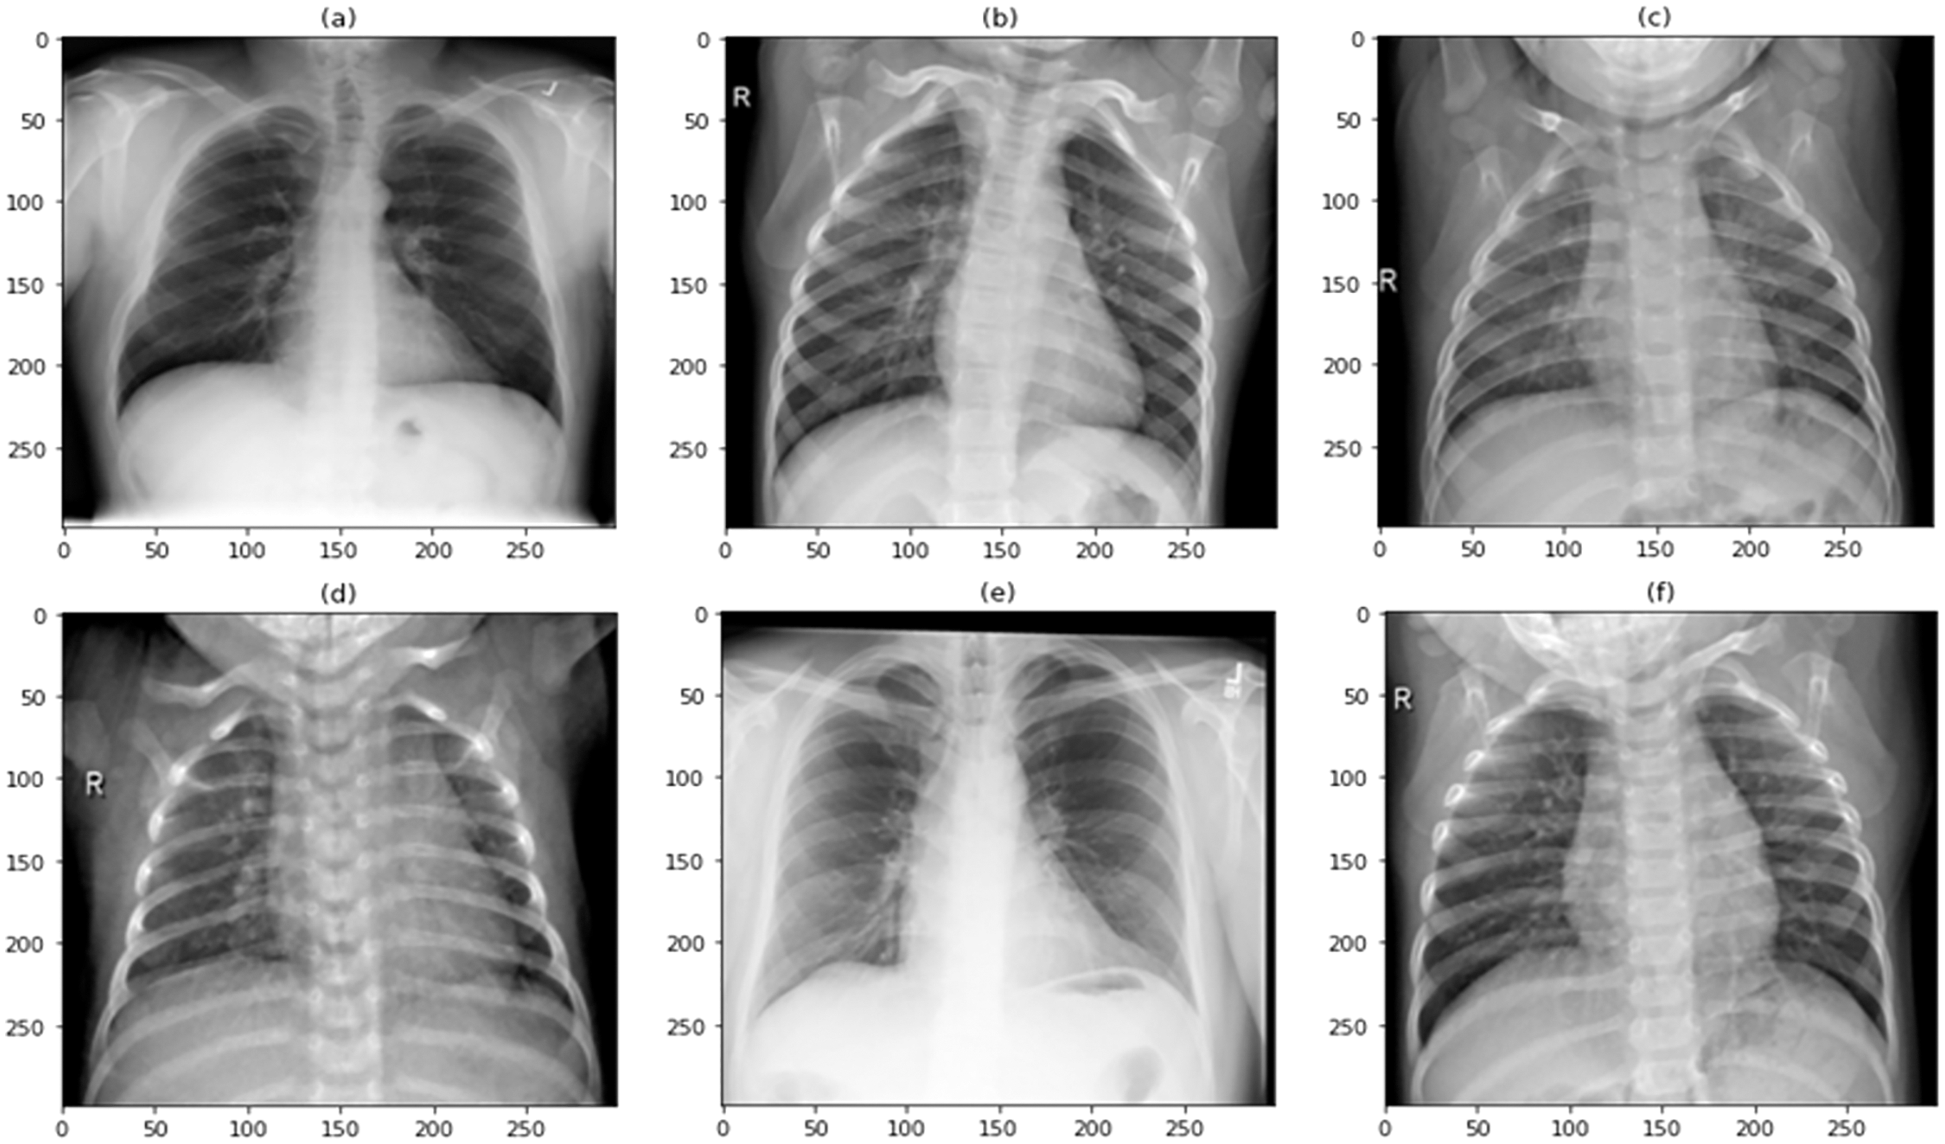

The diagnosis of COVID-19 was made using pulmonary (chest) X-ray scans in this research. COVID-19 and normal were the two main classes used to classify the data. A total of 9000 images were used in this study to train and test the proposed model. Out of a total of 9000 images, 6750 are used to train the model, accounting for 75% of the total, and 2250 are used to test the model, accounting for 25% of the total. Because the data in federated learning is decentralized and cannot have any association between the different sets, the dataset has been split into two sets, each of which is completely unique and has no correlation with the other set. A few examples of COVID-19 and Normal images, as well as augmented COVID-19 images, are exhibited in Figs. 1–3, respectively, before being split in two and moved to their corresponding edge nodes. These figures were taken before the images were divided in half. On the gathered dataset, image augmentation was performed by rotating 90 degrees, flipping 180 degrees, and further rotating 270 degrees. The COVID-19 and Normal image dataset distribution are displayed in Table 1, which is used for training, testing, and validation. Table 2 displays the distributed dataset to two separate edge devices and their corresponding test and train data. The reason for selecting different dataset for the two nodes is to display that it is capable of catering different edge nodes with different size of datasets.

Figure 1: Sample image dataset of COVID-19 patients

Figure 2: Sample image dataset of normal patients